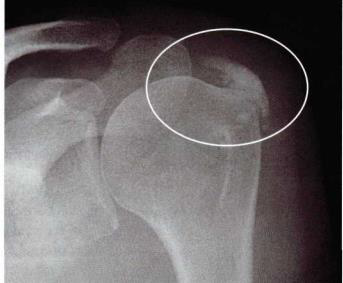

Observa-se acentuadas calcificações na topografia da inserção do tendão:

do supraespinhoso na cabeça umeral.